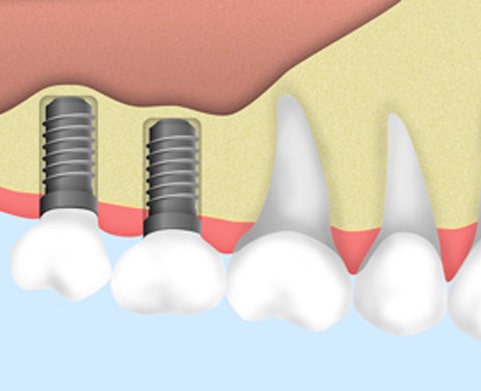

3ヶ月待って骨がしっかりできたら、インプラントを埋めます。

ネジを入れた状態で3ヶ月待って、そのあとインプラントを入れていきます。

約1週間程度で抜糸や消毒を行います。個人差がありますが、3~6ヶ月程度の安定期間をおきます。フィクスチャー(歯根部)と骨が結合する、大切な期間です。